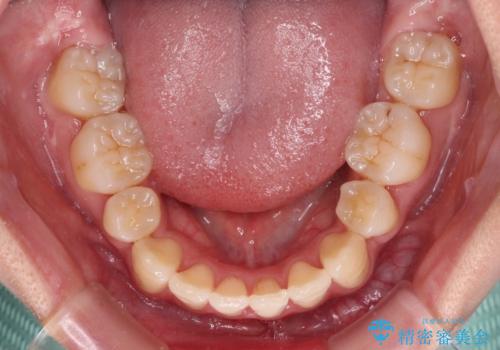

20歳前後と年齢が若かったため、非常にスムーズに歯列が整い、1年半をかけずに治療を終えることができました。